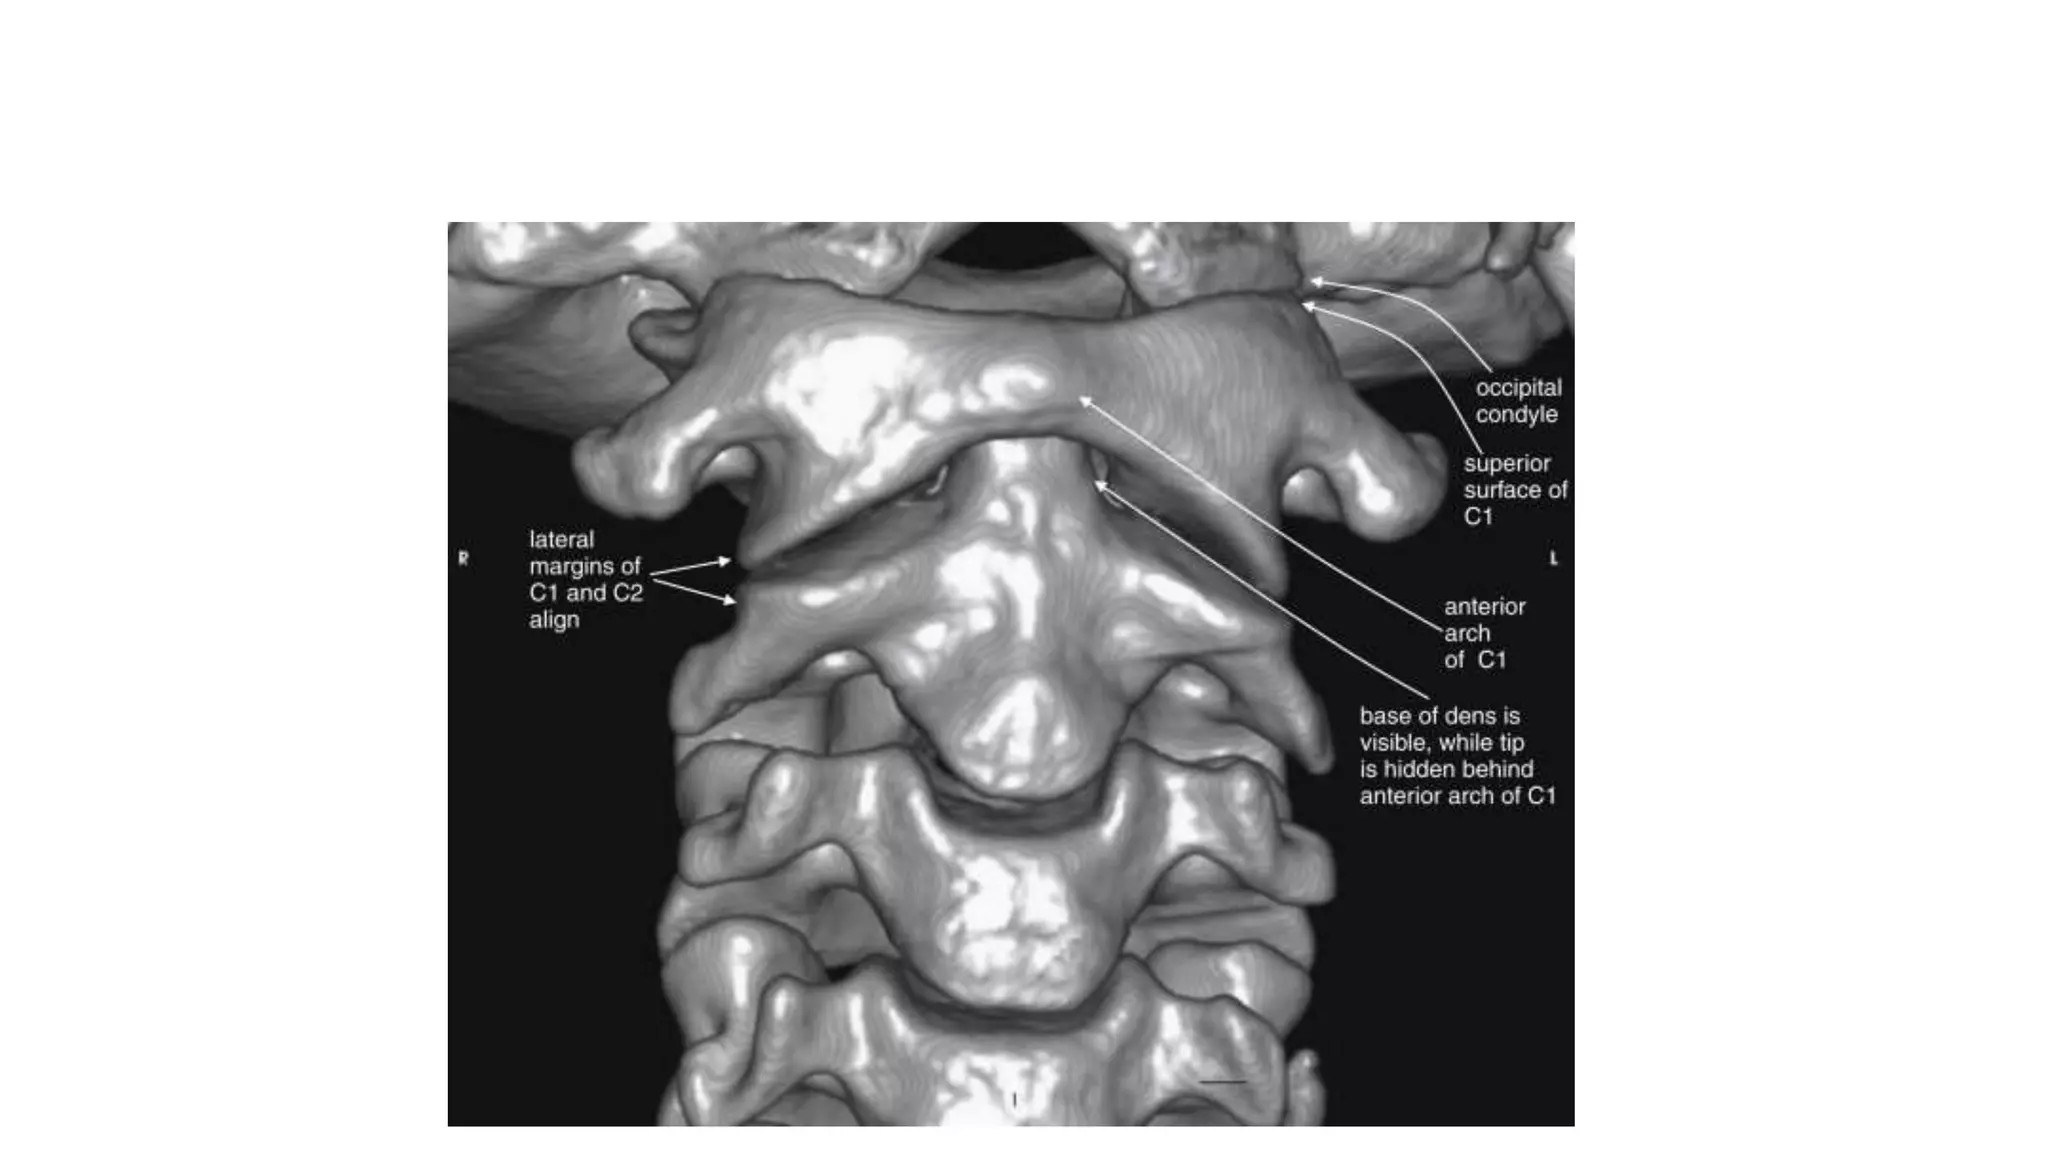

This three-dimensional reconstruction from computed tomography (CT) axial images focuses on the occipital–

cervical junction and the C1-2 (atlantoaxial) junction

The skull base has been cut away nearly completely in this

CT model, allowing the ring of C1 and its relationship to the

dens of C2 to be seen in detail.

C1 and C2 view of the normal cervical spine

This three-dimensional reconstructionfrom computed tomography (CT) axial images focuses on the occipital– cervical junction and the C1-2 (atlantoaxial) junction

• 13.

The skull basehas been cut away nearly completely in this CT model, allowing the ring of C1 and its relationship to the dens of C2 to be seen in detail. C1 and C2 view of the normal cervical spine